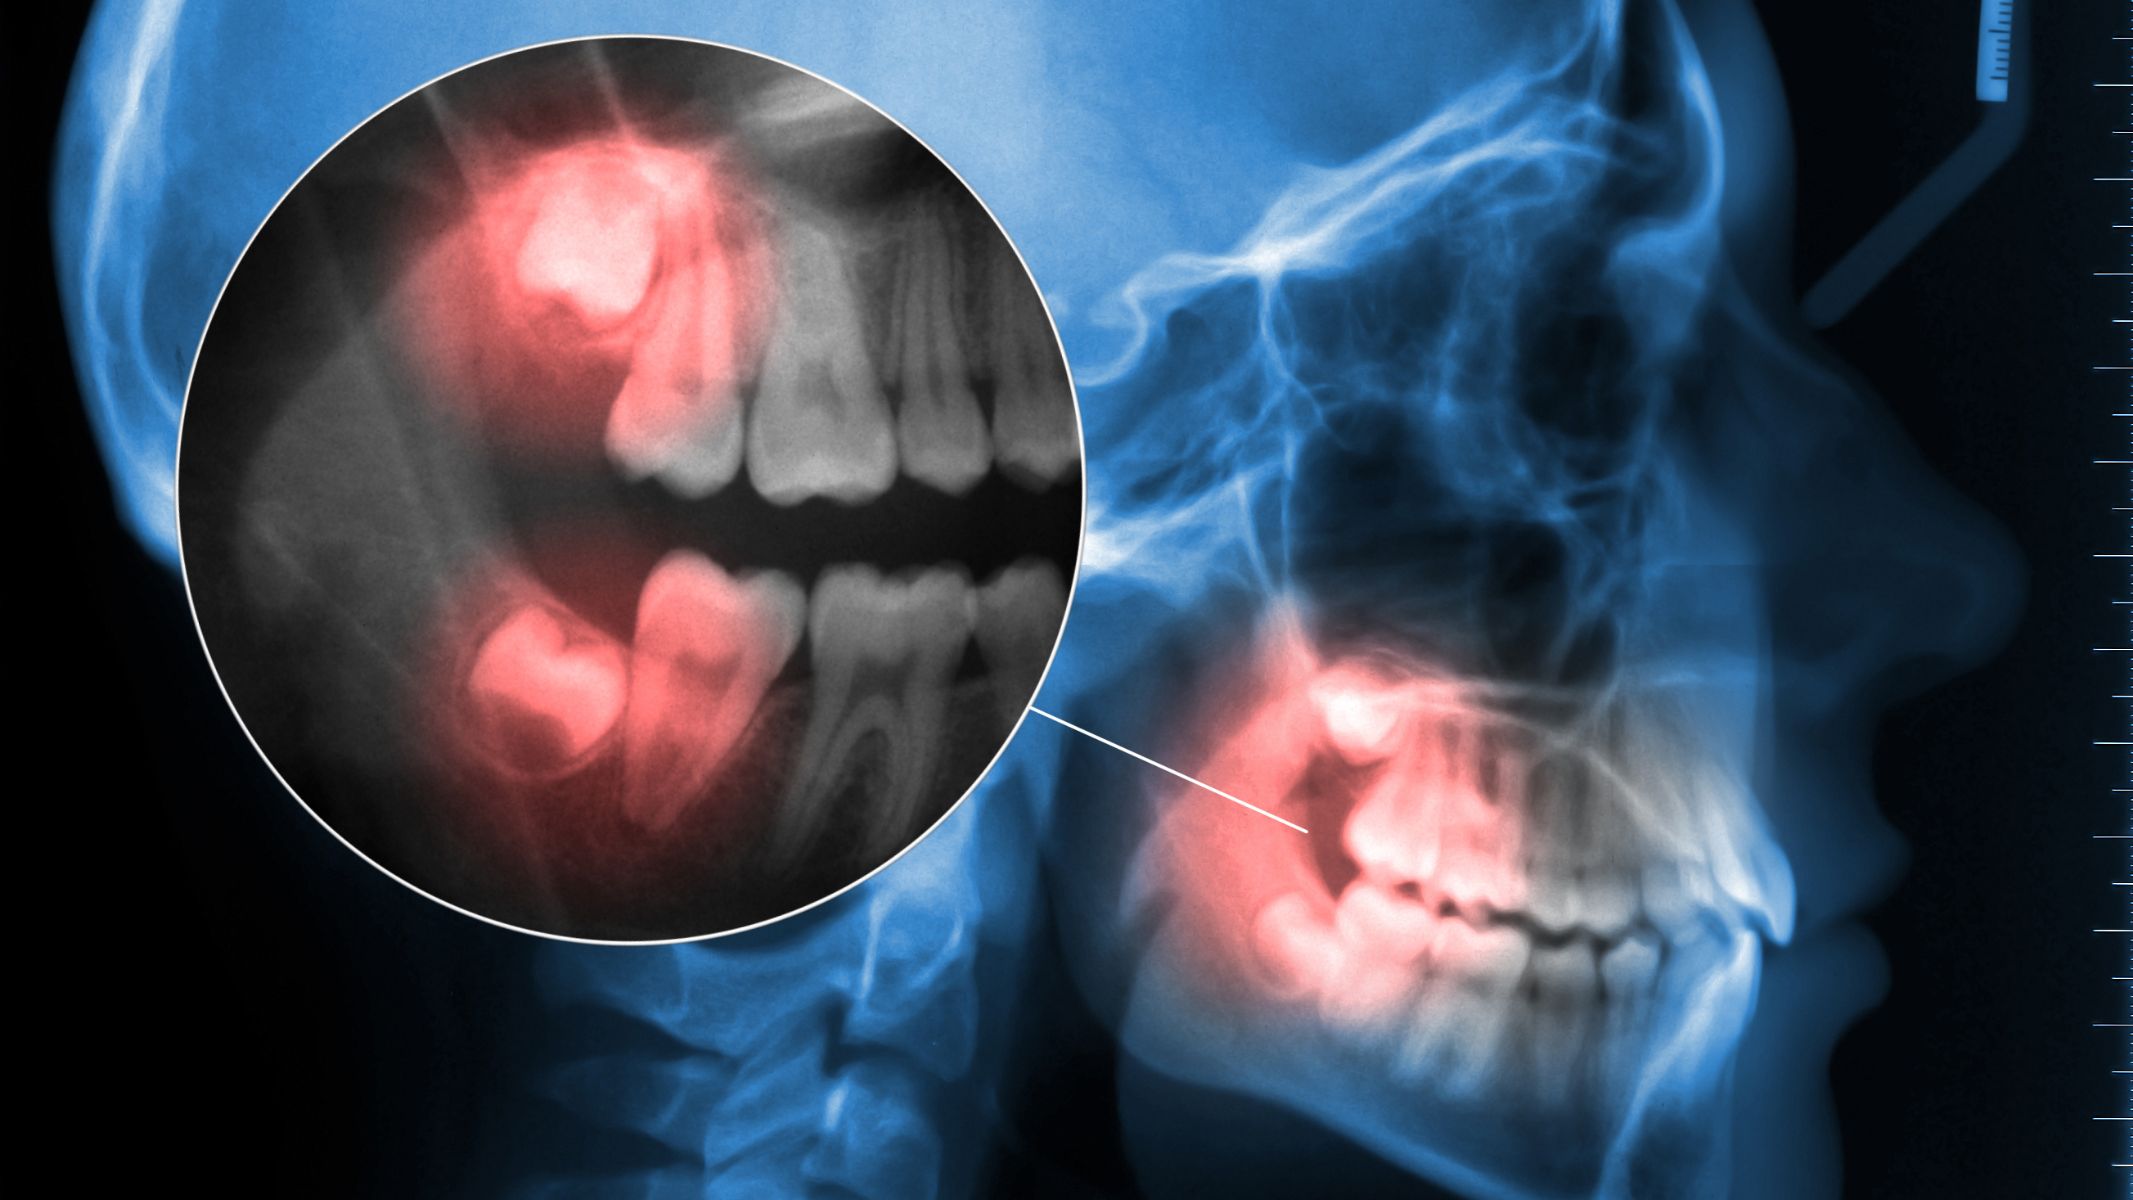

Cấu trúc chân răng khôn khá phức tạp, nên việc đánh giá số lượng và hình thái chân răng luôn được xem là bước quan trọng trước khi can thiệp điều trị hoặc nhổ bỏ.

Tuy nhiên, trên thực tế, răng khôn được xem là răng có mức độ biến thiên nhiều nhất trong cung hàm. Một số trường hợp có thể xuất hiện 4 chân hoặc thậm chí nhiều hơn, với hình dạng chân răng cong, xoắn hoặc hợp nhất. Chính sự thay đổi này khiến răng khôn dễ mọc lệch, mọc ngang, gây viêm nướu, sâu răng kế cận, thậm chí gây đau lan lên tai, đầu hoặc vùng thái dương.

Do cấu trúc chân răng phức tạp, bác sĩ thường chỉ định chụp X-quang hoặc CT Cone-beam trước khi nhổ răng khôn nhằm xác định số lượng chân răng, hướng mọc, mức độ ăn vào xương hàm và khoảng cách với dây thần kinh. Thông tin này giúp xây dựng phác đồ điều trị chính xác, hạn chế biến chứng và rút ngắn thời gian hồi phục cho người bệnh.